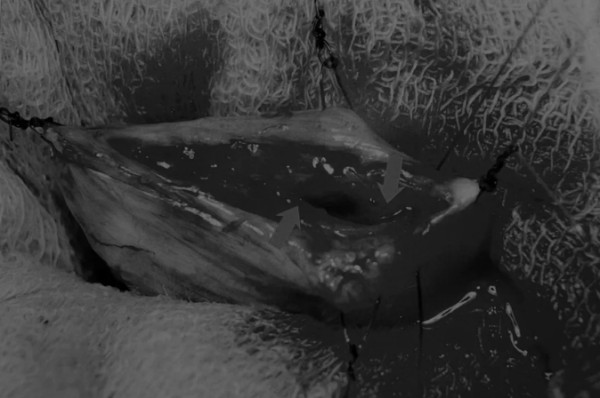

在中线开腹手术后,确定膀胱,将其取出并隔离(图1)。为了使膀胱持续暴露,可在膀胱中线两侧各放置一根固定缝线(图2)。

在牵引缝线之间选择血管扩张较差的区域用手术刀切开膀胱壁(图3)。在牵引缝合线之间用手术刀在血管不良的区域做切口。切开膀胱壁后,膀胱内的手术可按手术方案实施,例如取出结石(图4)。

图3 避开主要的膀胱血管,做一个尽可能小的切口